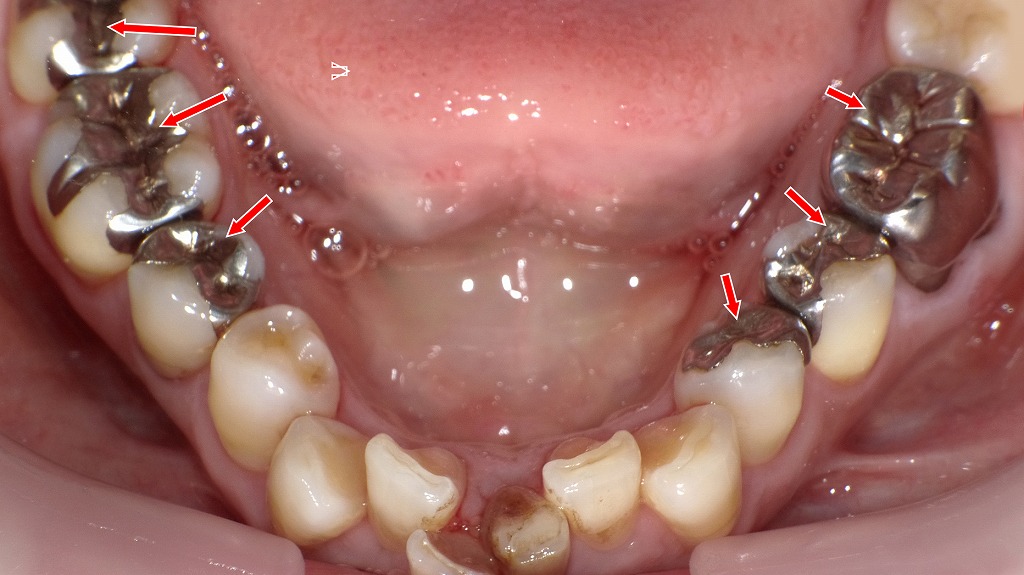

この画像の赤い矢印で示された部分に 保険診療で装着された金属の補綴物(銀歯) です。

🦷 上顎第二小臼歯(赤矢印上)

- 銀色の**クラウン(全部被せ物)**が装着されています。

- これは一般的に「保険の銀歯(メタルクラウン)」と呼ばれるものです。

- 金銀パラジウム合金(いわゆる“銀歯”)が使用されており、強度は高いものの、

金属色が目立つため審美性(見た目)に劣るのが欠点です。

🦷 下顎第一大臼歯(赤矢印下)

- 銀色の部分的な詰め物(インレー)が見えます。

- こちらも保険の金銀パラジウム合金インレーで、虫歯治療後の欠損部を補うために装着されたものです。

- 咬合面のみに金属が見える形で、クラウンよりも削る量が少ないのが特徴です。

- 長期間使用すると、二次う蝕(再び虫歯ができる)や金属の腐食・変色が起こることがあります。

🔍 まとめ

| 部位 | 補綴物の種類 | 材質 | 特徴 |

|---|---|---|---|

| 上顎第二小臼歯 | 銀歯(クラウン) | 金銀パラジウム合金 | 強度は高いが審美性に劣る |

| 下顎第一大臼歯 | インレー(部分的な詰め物) | 金銀パラジウム合金 | 保険適用、耐久性あり、見た目は劣る |

このような銀歯は保険適用で安価に治療できる利点がありますが、

最近ではより自然な見た目のセラミック・ハイブリッドレジンに変更する患者さんも増えています。